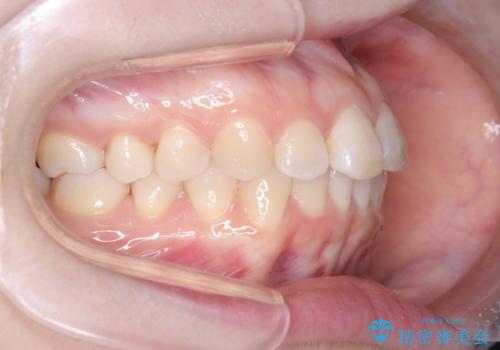

- 前歯のデコボコ(叢生)を気にされてご来院されました。精密な検査の結果、歯が並ぶスペースが不足していることが判明。患者様のご希望から、透明で目立ちにくいインビザライン(マウスピース矯正)による治療計画を立案しました。抜歯を避け、奥歯全体を奥へ動かす遠心移動という方法でスペースを確保し、前歯の叢生を解消することを目指します。

今回の矯正治療では、透明なマウスピース型の装置インビザラインを使用しました。この装置は取り外し可能で、日常生活で目立ちません。治療は、緻密に計算された計画に基づき、段階的に作製されたマウスピースを交換していくことで、奥歯から順に全体を後方へ移動させる遠心移動を実施。これにより、前歯を並べるための十分なスペースが確保され、デコボコが解消されました。抜歯することなく、機能的にも審美的にも整った美しい歯並びを獲得していただけました。